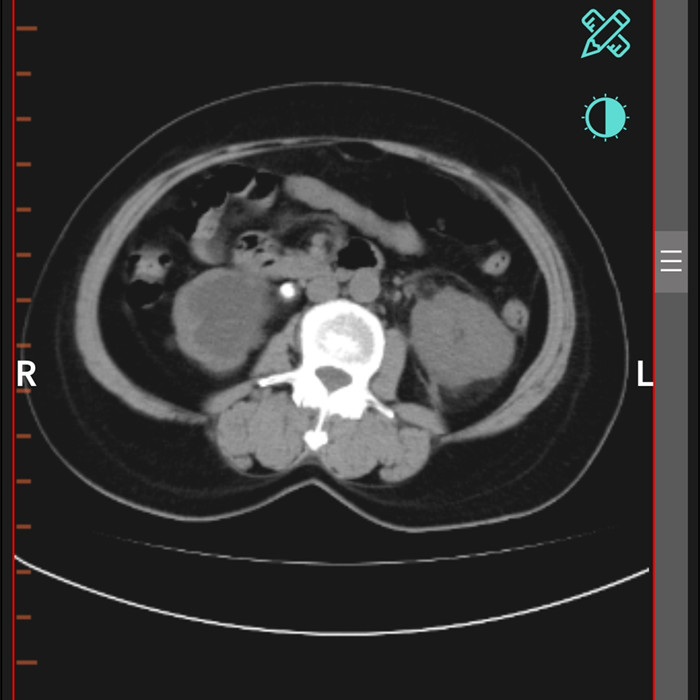

柴女士,62歲,北川縣擂鼓鎮(zhèn)人,因腰右側(cè)疼痛難忍,她來(lái)到北川羌族自治縣人民醫(yī)院就診,經(jīng)檢查提示,柴女士右輸尿管上段結(jié)石嵌頓引起重度腎積水。

“要及時(shí)解除梗阻,可以行腹腔鏡輸尿管切開(kāi)取石術(shù)取代開(kāi)放手術(shù)?!痹谥靹τ碌膸ьI(lǐng)下,這支剛剛成立的“泌尿外科團(tuán)隊(duì)”,僅用了一個(gè)半小時(shí)就完成了手術(shù)。“腹腔鏡輸尿管切開(kāi)取石術(shù)創(chuàng)傷小,患者腰腹部只有3個(gè)戳孔,術(shù)后恢復(fù)快?!敝靹τ抡f(shuō)。